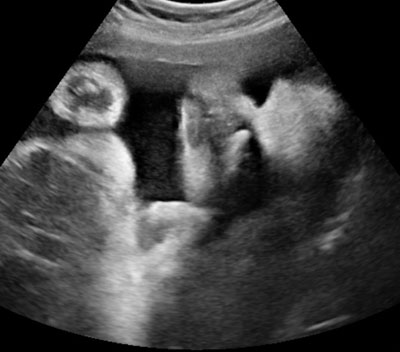

УЗИ на 32 неделе беременности

В этот период УЗИ проводят трансабдоминально, т.е. трансдермально. Обследование вагинальным зондом не проводится, даже если имеется ВЧГ и имеется пессарий (или шейка матки ушита). Это связано с риском преждевременных родов на этом критическом этапе беременности.

Нормальная (двумерная) допплеровская сонография занимает около 20 минут. При необходимости (если возникает вопрос о запутывании пуповины) или если мы хотим выполнить трехмерное или четырехмерное ультразвуковое исследование в офисе, мы будем придется потратить не менее 40 минут.